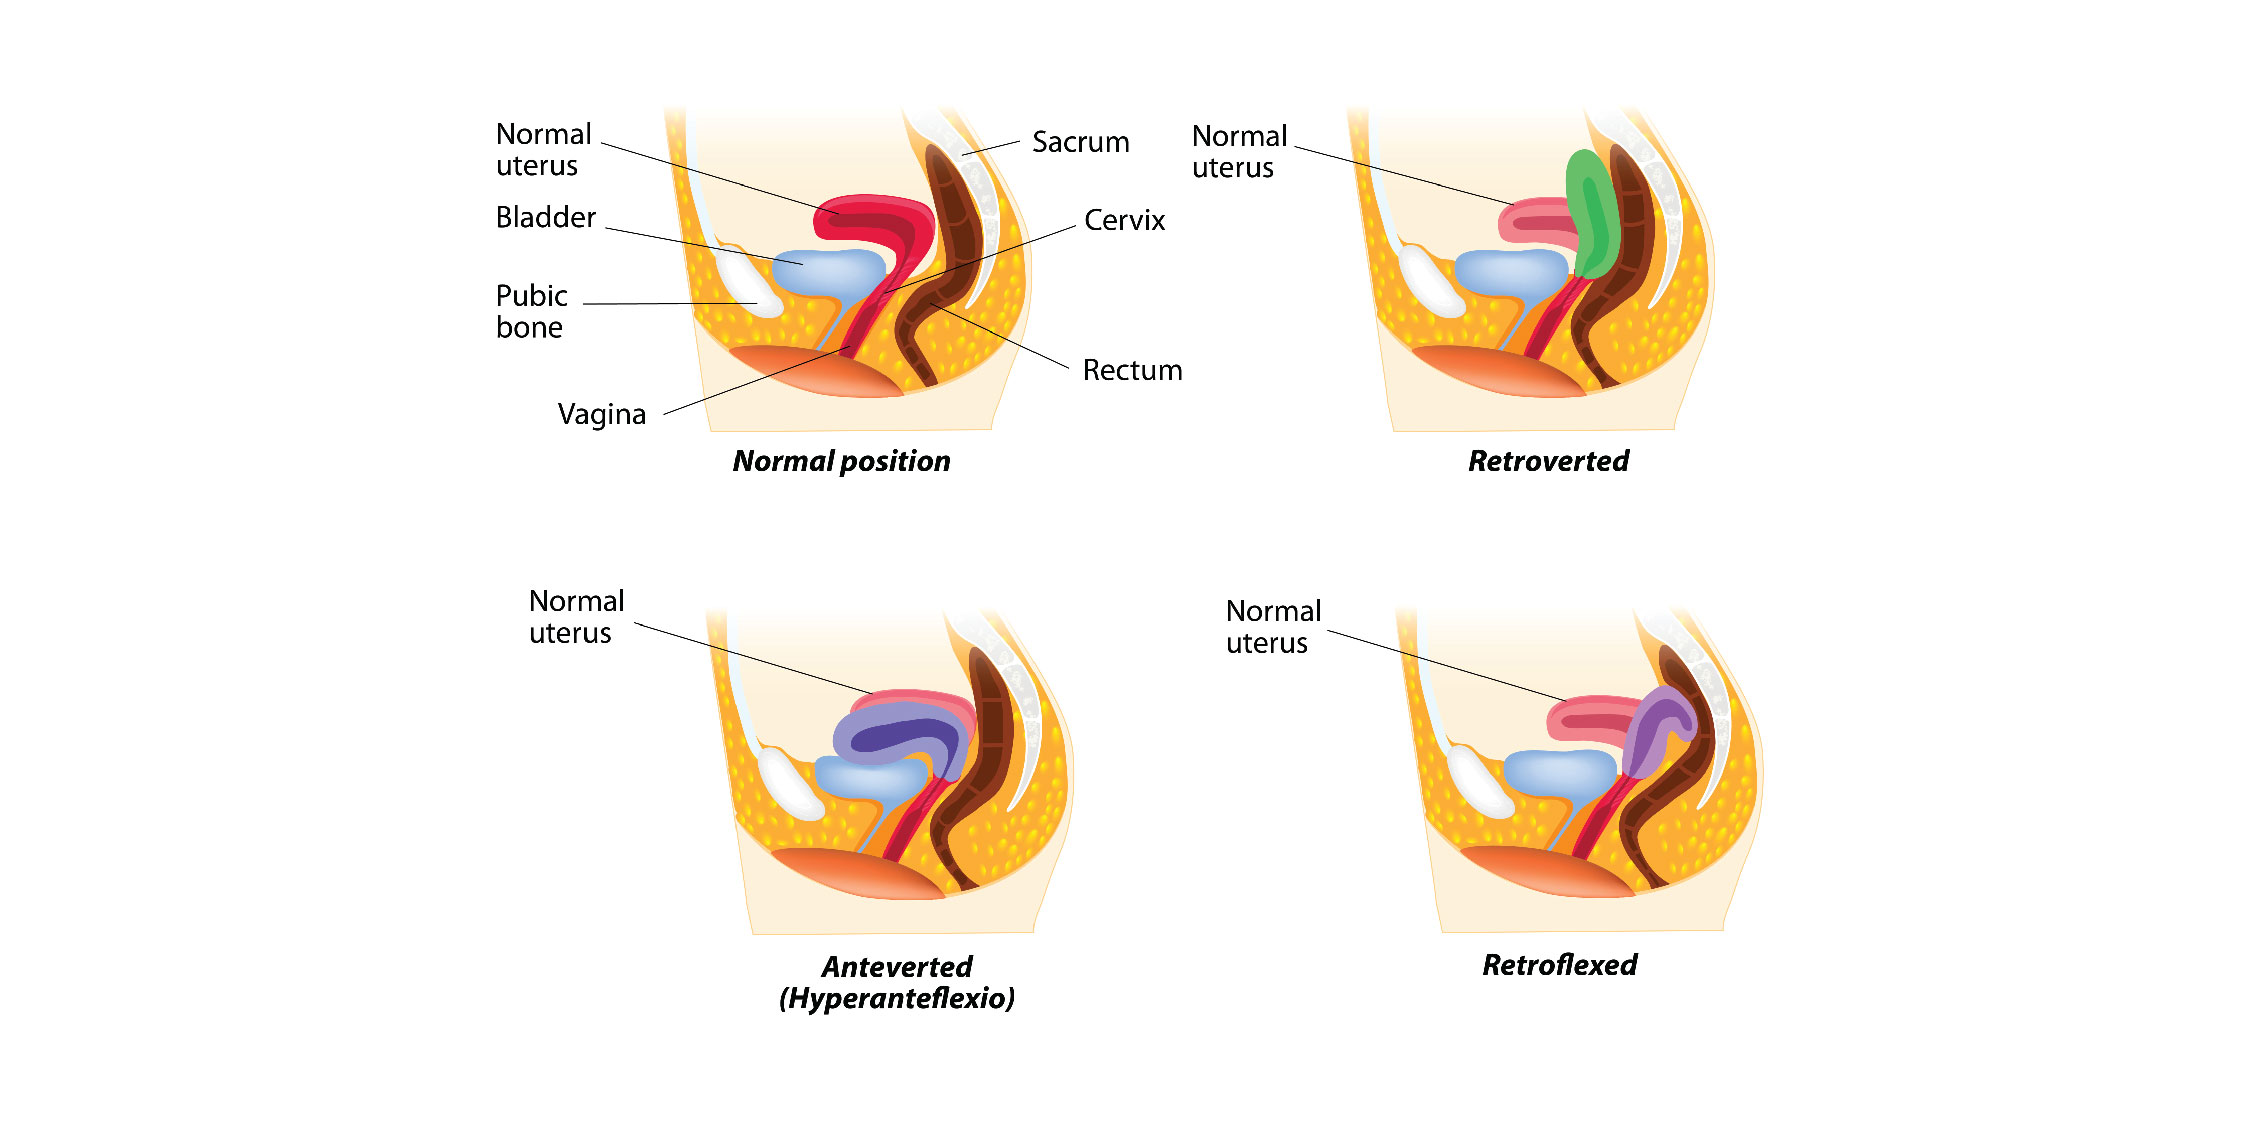

Plasenta Previa - Pengertian dan Penyebab

Plasenta Previa - Pengertian dan Penyebab

4 Jenis Plasenta Previa dan Faktor Penyebabnya | Popmama.com

4 Jenis Plasenta Previa dan Faktor Penyebabnya | Popmama.com

Posisi Sujud untuk Plasenta Previa, Efektifkah?

Posisi Sujud untuk Plasenta Previa, Efektifkah?